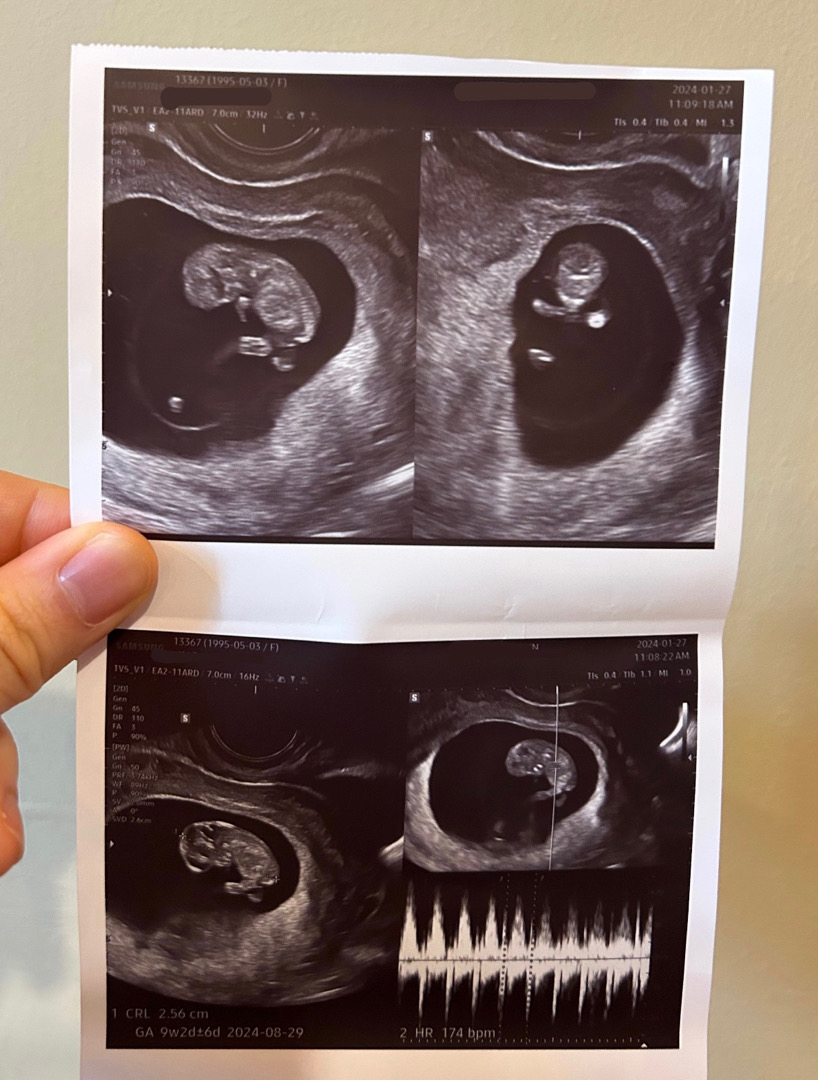

젤리곰(9주 4일)

지난주에 병원갔을때 의사선생님이 이제 한달 뒤인 12주에 오세요~ 했는데 입덧도 전처럼 하루에 두번씩 토하지 않고 하루 건너 한번 토하길래 불안한 마음 갖느니 방문하자!하고 남편이랑 다녀왔네요ㅎㅎ 작년에 이맘때쯤 방문했을 때 갑자기 심장이 안뛴다고 해서 소파술 한 경험이 있어서 병원가기 전에 긴장감 최고조였어요..ㅠㅠ 다행히도 9주 4일차로 젤리곰 보고 왔어요🤍💛🤍 팔다리 생긴 것도 신기하고, 척추도 그리고 제눈에는 손가락 발가락도 보이는 것 같네요ㅋㅋㅋ 첫번째 사진보고 팔은 두개 맞죠 선생님..? 하니까 두번째 사진으로 두 팔을 보여주셨어요☺️☺️ 짧은 다리는 왜 저렇게 꼬고 있는지ㅋㅋㅋ 기존병원은 일주일만에 또 가기 민망해서 새로운 병원으로 갔는데, 보험적용도 한번 더 받고 좋은 꿀팁인 것 같아요!! 뽀롱이가 건강하게만 잘 자라줬으면 하네요🩵